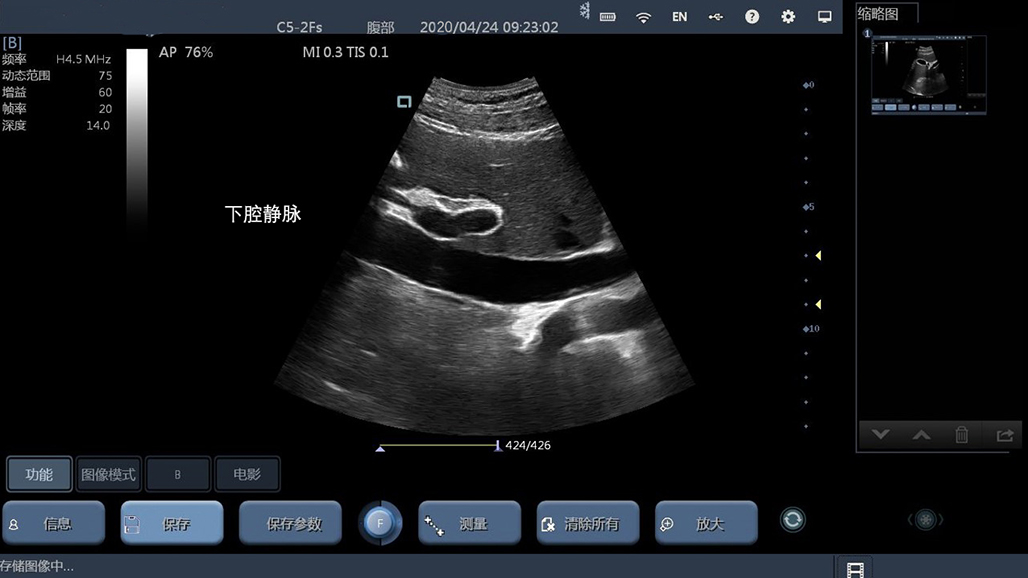

• 微凸

腹部

肾脏

新生儿颅脑

及心脏

小动物等